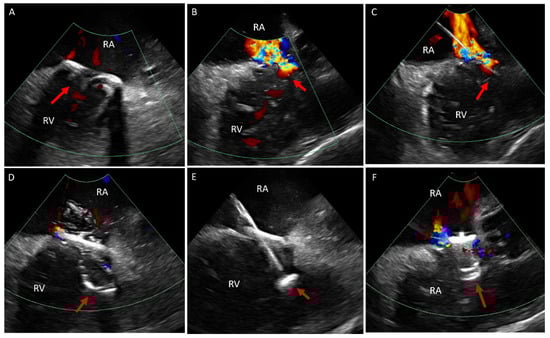

5.2. Transcatheter Tricuspid (Right Atrioventricular) Valve in Valve or Valve in Ring Replacement (TVIV/TVIR)

- Sanon, S.; Cabalka, A.K.; Babaliaros, V.; Rihal, C.; Gafoor, S.; Webb, J.; Latib, A. Transcatheter Tricuspid Valve-in-Valve and Valve-in-Ring Implantation for Degenerated Surgical Prosthesis. JACC Cardiovasc. Interv. 2019, 12, 1403–1412. [Google Scholar] [CrossRef] [PubMed]